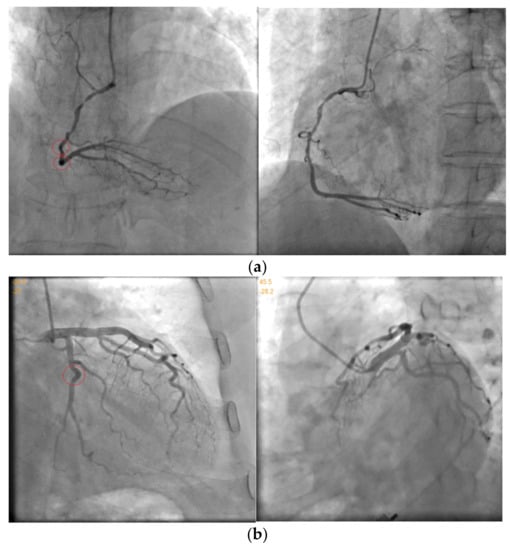

Table 2 evaluates the systematic parameters optimization algorithm by some kind of index. Figure 8. shows the accuracy of the epipolar line of calculating by the optimized systematic parameters. The data used in Figure 8 is Data.1 because its initial error is the biggest.

Figure 8.

Matching results after different optimization. (a) is the result of Match 1; (b) is the result of Match 1; (c) is the result of Match 1; and (d) is the result of Match 1.

It can be seen that the accuracies of the epipolar line after all the three kinds of optimization are similar for matching. So, the main concerns are optimization efficiency and robustness.

In Table 2, because of the cooling strategy of Optimize 1, the fixed 695 times iterations, which will waste a lot of time, and the instability of the results limits its clinical application. As for Optimize 2, it cannot achieve the target error in Data.1 and Data.2, which means it will fall into the local optimal solution. The convergence of Optimize 3 is far superior to other methods, reaches the ideal limit error, and can meet the high-precision requirements in clinical practice. At the same time, the iterations number and optimization time of Optimize 3 is also the smallest, which has greater advantages compared to other methods.

In order to evaluate the effect of our proposed algorithm on improving the accuracy of the 3D reconstruction, the directly matching method relying on the order of points on blood vessels is recorded as Match 1, the dynamic programming algorithm with fixed step size is recorded as Match 2, and the dynamic programming algorithm with self-adaption step size according to CBOCD proposed in this paper is recorded as Match 3. Finally, we assume that the traditional method only uses epipolar line constraint as Match 4.

Clinical studies indicate that to evaluate the accuracy of matching point pairs, it is necessary to compare the same feature points matching in the blood vessel segment. As shown in Figure 8, from Match 1 to Match 4, the smoothness of conjugate point pairs decreased gradually. The result of Match 4 even has some mismatches. In other words, when there are multiple intersections between the vessel and the epipolar line, the matching points that do not conform to the smoothness of blood vessels are selected by mistake. So, Match 4 cannot be used in the 3D reconstruction of blood vessels.